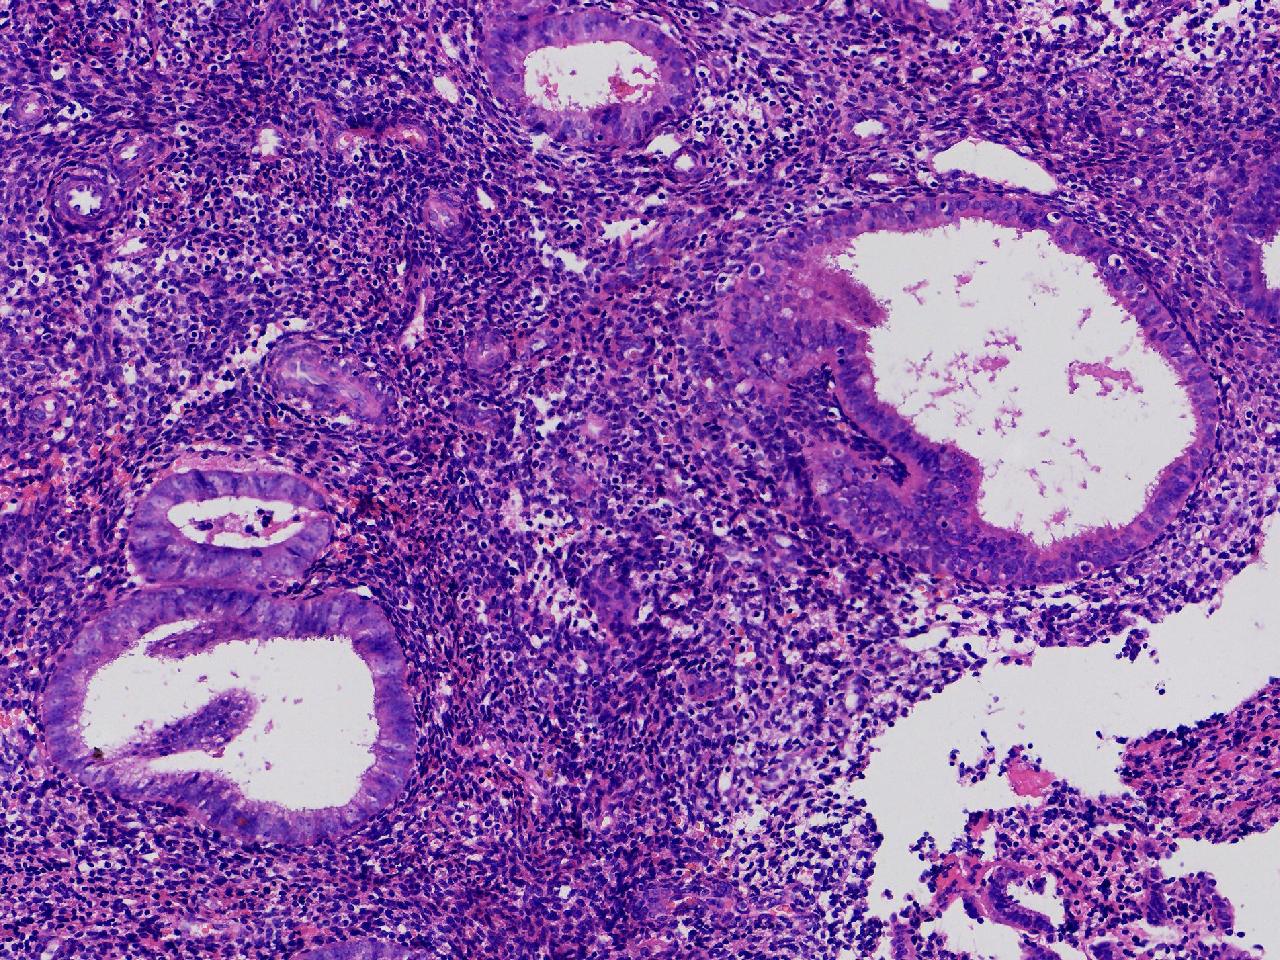

请教诊断。局灶够不够非典?

阴道不规则出血20余日,彩超示:内膜线居中,厚15毫米。

子宫内膜

灰粉色不整形软组织多块,3X2X1厘米。

不够非典

有输卵管上皮化生,感觉不够非典。